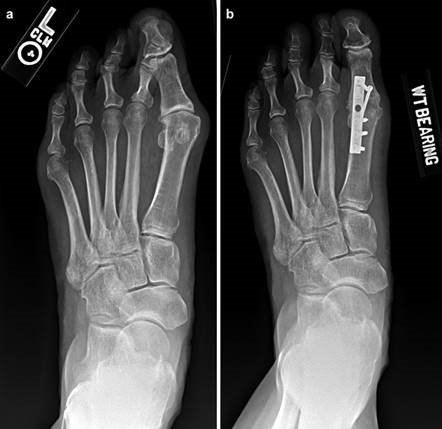

Weight-bearing anteroposterior (AP), lateral, and sesamoid axial radiographs are mandatory. On the AP view, the surgeon measures the Hallux Valgus Angle (HVA, normal < 15°), the Intermetatarsal Angle (IMA, normal < 9°), and the Distal Metatarsal Articular Angle (DMAA). The lateral view is scrutinized for Meary's angle (talo-first metatarsal angle) to identify midfoot collapse, as well as the presence of dorsal osteophytes indicative of hallux rigidus. The sesamoid axial view is critical for assessing the degree of sesamoid subluxation and the integrity of the crista.

Digital Templating and Patient Positioning

Digital templating software is employed to determine the center of rotation of angulation (CORA) and to simulate the proposed osteotomy or fusion. This allows the surgeon to anticipate the degree of translation required, the potential for metatarsal shortening, and the appropriate size of fixation hardware. For a Lapidus procedure, templating helps calculate the exact wedge of bone to be resected from the medial cuneiform and first metatarsal base to achieve the desired multiplanar correction.

A V-shaped osteotomy is then created in the metatarsal neck with an apex angle of approximately 60 degrees. The apex is positioned centrally within the metatarsal head, and the limbs exit dorsally and plantarly. The capital fragment is translated laterally by 30-50% of the metatarsal shaft width. If the DMAA is increased, a medial closing wedge can be incorporated into the osteotomy. The osteotomy is provisionally stabilized with a Kirschner wire, and definitive fixation is achieved using one or two headless compression screws directed from dorsal-proximal to plantar-distal. The medial capsule is then imbricated to correct the soft-tissue imbalance, and the skin is closed in layers.

To achieve multiplanar correction, the surgeon must address the sagittal, coronal, and transverse planes. The first metatarsal is plantarflexed to restore the longitudinal arch, rotated out of pronation to realign the sesamoids, and translated laterally to close the IMA. Subchondral drilling or feathering is performed to optimize the biological environment for fusion. Fixation is traditionally achieved with two or three crossed solid or cannulated screws (typically 3.5mm or 4.0mm). Recently, plantar or medial locking plates have gained immense popularity due to their superior biomechanical construct, allowing for earlier weight-bearing. Bone graft or orthobiologics may be packed into the arthrodesis site to stimulate osteogenesis.